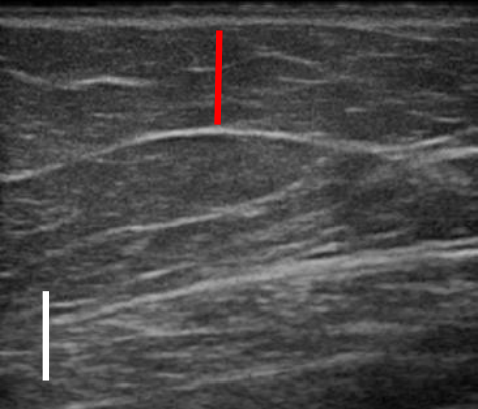

실제 지방이 어느 정도 감소했는지는 초음파 사진을 보면 더욱 뚜렷하게 확인할 수 있는데.

트루스컬프ID 시술 전, 12주 후

초음파를 비교한 사진입니다.

레드 라인이 지방층의 두께입니다.

앞서 보여드린 사례의 경우 시술 전과 비교했을 때 약 36% 정도 지방이 감소한 결과를 볼 수 있는데요.